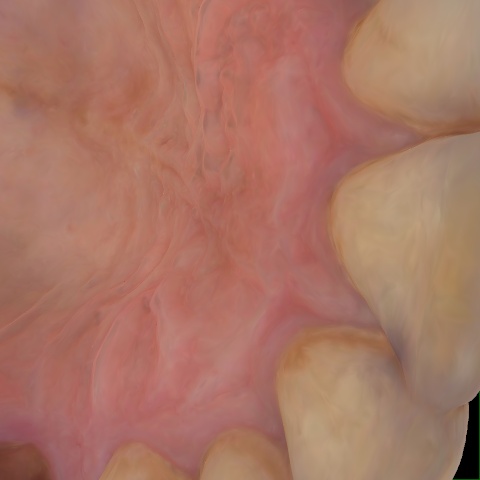

Image 362 / 1743

NHD36692

Annotated as "Good"

Original Image Rendering Image